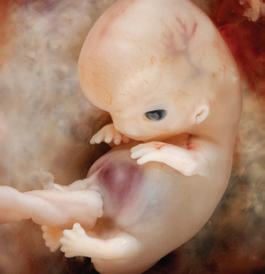

Day 1: Fertilization

The sperm joins with the egg to form one cell. This single cell contains the complex genetic makeup for every detail of a new human being. After fertilization, nothing new is added but oxygen, nutrition and time.1

1st Month: 1–4 Weeks

The first cell divides in two, and cell division continues as it travels down the fallopian tube to the uterus. Foundations of the brain, spinal cord, and nervous system are already established and by day 21 the heart begins to beat in a regular fashion.2 Muscles are forming, and arms, legs, eyes, and ears have begun to show.

2nd Month: 5–8 Weeks

By six weeks, brain waves can be detected.3 The jaw forms, including teeth and taste buds.4 The baby begins to swallow amniotic fluid, and sometimes hiccups.5 Fingers and toes are developing and at seven weeks the chest and abdomen are fully formed.6 Swimming in the amniotic fluid, she now looks like a miniature human infant.7,8

3rd Month: 9–12 Weeks

Unique fingerprints are evident and never change.9 The baby now sleeps, awakens, and exercises her muscles. The baby is very active. The gender can be visually determined and family resemblances may appear.10 At the end of the first trimester, all the organs and systems of her body are functioning.11

4th Month: 13–16 Weeks

By the end of the fourth month, the baby is 8–10 inches in length and weighs about one-half pound. Her ears are functioning and she hears her mother’s heartbeat, as well as external noises like music.12 Lifesaving surgery has been performed on babies at this age.

5th Month: 17–20 Weeks

If a sound is especially loud, the baby may jump in reaction to it. Thumb-sucking has been observed during the fifth month.13

6th Month: 21–24 Weeks

Oil and sweat glands are functioning. She grows rapidly in size and strength while her lungs become more developed.14

7th Month: 25–28 Weeks

The baby can now recognize her mother’s voice. She exercises by stretching and kicking. She uses the senses of hearing, touch and taste, and she can even look around with open eyes.15

8th Month: 29–32 Weeks

The baby swallows a gallon of amniotic fluid per day and often hiccups.16 The baby’s kicks are stronger and mom may be able to feel an elbow or heel against her abdomen.17

9th Month: 33–36 Weeks

Gaining one-half pound per week, the baby is getting ready for birth. The bones in her head are soft and flexible to more easily mold for the journey down the birth canal.18 Of the 45 generations of cell divisions before adulthood, 41 have already taken place. Only four more come before adolescence. Ninety percent of a person’s development happens in the womb.19